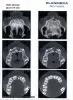

Ваш зуб спасти невозможно и рекомендую не тянуть, и быстренько удалять.